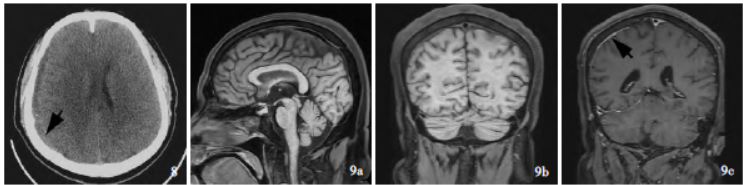

图8 靶向自体血硬膜外血贴术后(2021年11月4日)横断面CT显示,双侧硬膜下血肿吸收,残留少量右侧额顶叶硬膜下积液伴血性成分(箭头所示) ;图9 出院后3 个月(2022 年2 月18 日)MRBTI所见,9a 矢状位MRBTI显示上矢状窦血栓吸收,9b 冠状位MRBTI显示左侧顶叶皮质静脉血栓吸收,9c 冠状位增强MRBTI仅显示右侧顶叶脑膜轻度强化(箭头所示)

于入院第21 天(11 月1 日)行靶向自体血硬膜外血贴术(图7),术中向硬膜外腔注入自体血约40 ml,术后2 天头痛症状消失;术后3 天(11 月4 日)脑脊液压力135 mm H2O(表1),CT显示双侧硬膜下血肿吸收,右侧额颞顶叶残留少量硬膜下血肿,无脑室受压(图8)。继续予以低分子量肝素0.80 ml/12 h抗凝治疗7天。出院前(11月9 日)再次复查脑脊液,压力为190 mm H2O(表1),脑脊液免疫球蛋白和血清IL-6 趋于正常(表2),共住院31 天,出院后遵医嘱服用达比加群110 mg/次(2 次/d)。随访至出院后2 个月,未再出现头痛,CT显示硬膜下血肿消失;出院后3 个月,MRBTI未见明确血栓征象,且增强扫描仅右侧顶叶硬脑膜呈轻度强化(图9),停用达比加群。